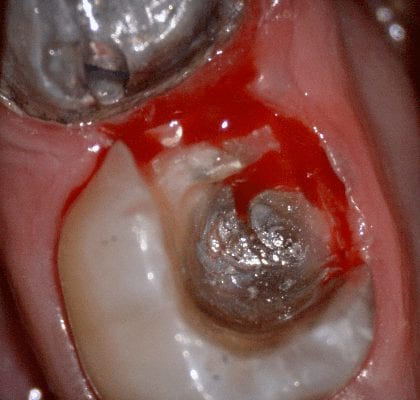

In this video we demonstrate some of the most common problems associated with second molar impressions. Usually the distal margins can be blurred by the presence of hemorrhaging or soft tissue. In this particular case, we use the tip of the camera to displace the tissue and digitall correct an area for better accuracy. The isolite systemisolite systemisolite system does a great job controlling the tongue and the lips and with proper retraction you can image a quadrant in very little time